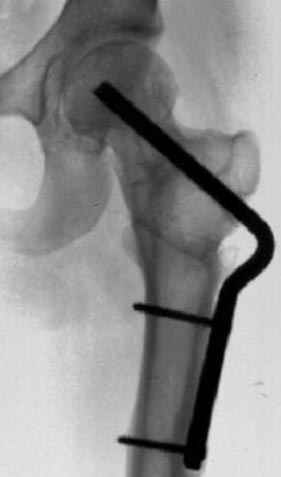

сустава, репозиция вывиха (N4), фиксация фрагмента 2.7(4) мм шурупами и допольнительно реконструктивной пластиной на 8 дырок, фиксация 3.5мм шурупами проксимально и дистально.

Интраоперционные N5 косая запирательная и N6 подвздошный снимок

11:50 больной в послеоперационной, рентгенограмма N7, компьютерная томограмма в тот же день N8-10